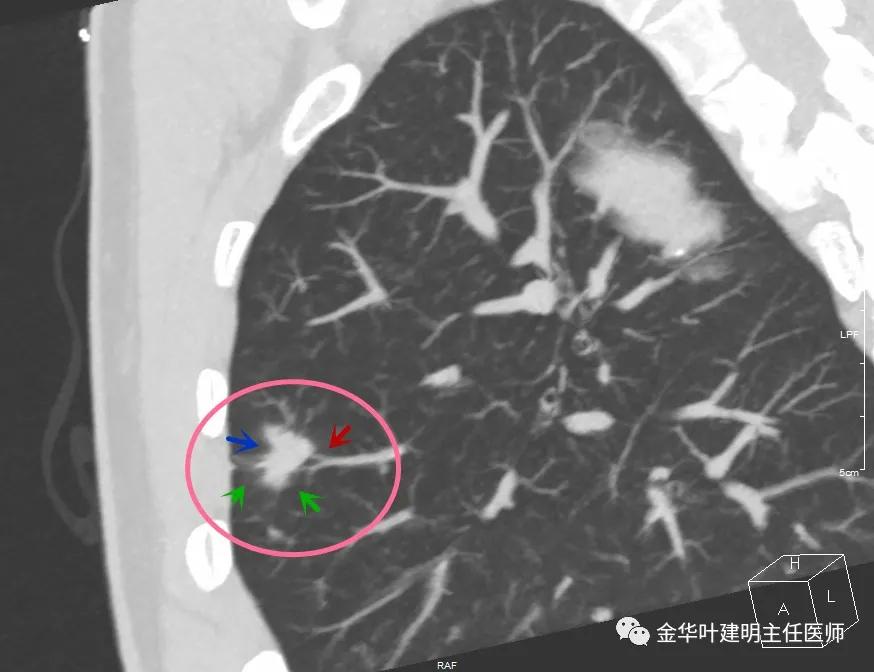

此层面红色箭头示有卫星灶,粉色箭头示主病灶

红色示卫星灶,粉色示病灶,绿色示边缘晕征

此层面相对最不舒服,病灶表面不平整。桔色箭头示血管进入病灶,但仍有绿色箭头示病灶有晕征(边缘是模糊的,不似肿瘤那种细毛刺且相对清楚轮廓)

上图红色箭头示仍有血管进入,但蓝色箭头示边缘内凹,绿色示仍有晕征

上图红色箭头示血管进入病灶